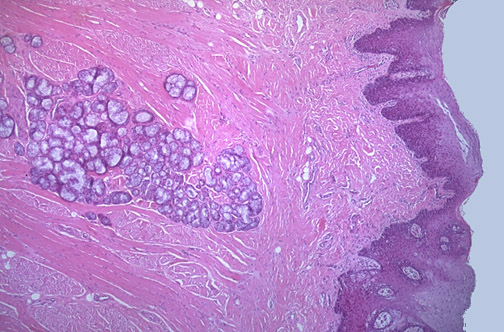

| At low power, the normal tongue has an overlying squamous epithelium beneath which is a lamina propria. The bulk of the tongue is composed of skeletal muscle. Scattered throughout the tongue, but more prominent toward the back of the tongue, are minor salivary glands. |